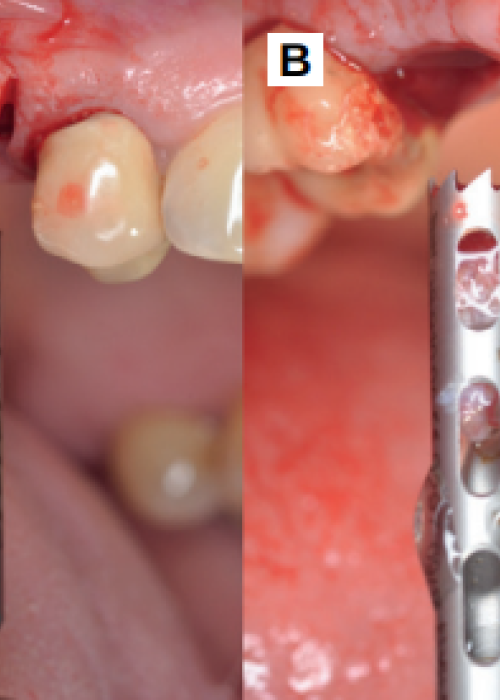

Reubicación quirúrgica de un segundo molar inferior. Presentación de un caso clínico y revisión de la literatura